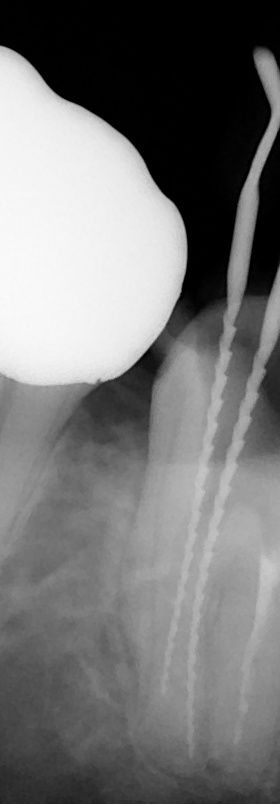

2根のところにリーマーを入れて、レントゲンを撮ったところです。

最初の時のレントゲンと比べてみるとわかりますが、近心根の赤い点線の部分が汚れていました。

最初のレントゲン

今 現在 拡大 清掃中です